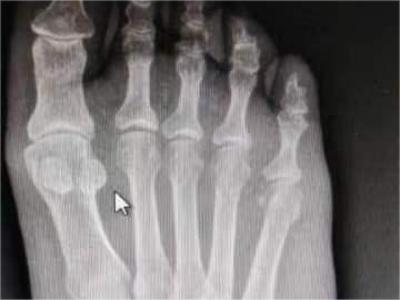

痛风性关节炎好发于40岁以上男性,多见于第一跖趾关节,也可发生于其他较大关节,如踝部关节、膝关节、手指关节等,表现为突然出现的关节肿胀和剧痛,受累关节及其周围软组织明显发红、发热和肿胀,剧痛难忍,以及关节活动受限,伴有痛风石的形成和慢性关节变形。

痛风性关节炎是众多关节炎类型中的一种,是由于血尿酸增高,尿酸盐结晶在关节、滑囊、软骨、骨质或关节周围组织以结晶形式沉积,并引起一系列炎症反应所造成,高嘌呤食物、饮酒、受冷或劳累等因素易诱发痛风。